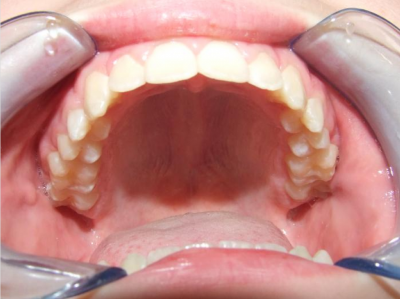

Behandeling Raoul

Duur

van 13-3-14 tot 16-9-15

Beschrijving

Leeftijd bij aanvang: 10 jaar

Bonded Hyrax + volledig vast onderkaak

Volledig vast bovenkaak + expander

Wrap + c-c bar onderkaak

Leeftijd bij afname: 12 jaar

Voor behandeling

Na behandeling